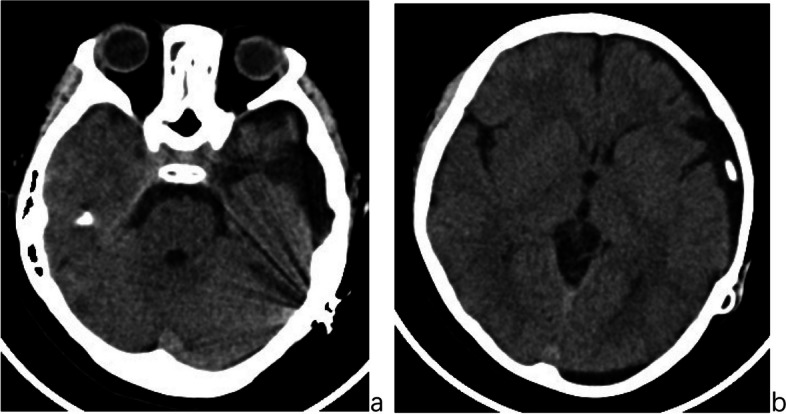

Case presentation: A child with a ruptured giant arachnoid cyst in the left middle cranial fossa presented with acute intracranial hypertension following head trauma. The initial cysto-peritoneal shunt surgery rapidly alleviated symptoms, including headaches, vomiting, and left cranial nerve palsy, stabilizing the clinical condition. However, between 20 and 24 months after the initial shunt surgery, the patient developed intermittent shunt dysfunction, experiencing recurrent headaches and vomiting, during which the programmable valve's pressure setting had become fixed and was no longer adjustable. A second surgery was then performed to remove the existing shunt, excise the fibrotic cyst wall, fenestrate the basal cistern, and establish temporary subdural drainage. During this operation, extensive fibrosis of the cyst wall in the subdural space was discovered, forming a tough and hypertrophic fibrotic membrane that encased the cerebral hemispheres. This fibrotic material nearly filled the shunt valve chamber, causing valve obstruction and immobilizing the pressure control rod, resulting in pressure adjustment dysfunction. As the patient could not maintain stability without continuous drainage, a third surgery was ultimately necessary to place a subdural-peritoneal shunt. Five years of follow-up revealed no significant clinical symptoms, and the patient has maintained a normal life.